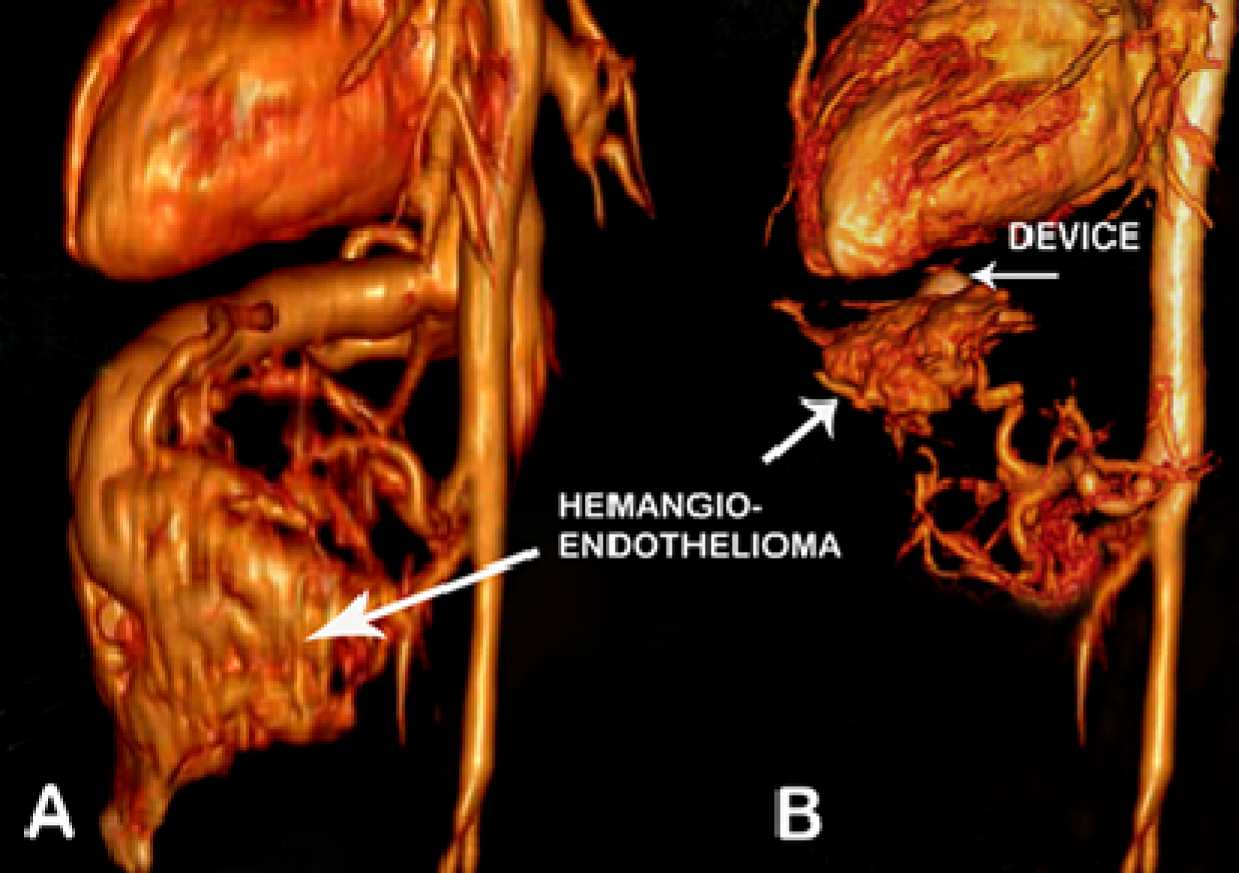

Terumo catheter. Almost complete cessation of flow through the anomalous channel was achieved by instillation of PVC particles at the end. The care was taken so that the diluted contrast containing PVC particles did not reflux into the celiac plexus. Once the check angiogram showed good occlusion of the mass, the ADO II device was released. Post procedure angiogram showed no flow into the hepatic lesion from the arterial end and the device was in good position at the venous end (Fig. 2D). The highly vascular lesion before procedure (Fig. 3A) regressed completely post procedure with the device in situ (Fig. 3B). The patient developed distension of upper abdomen after the procedure. This was treated conservatively as peristaltic sounds were well heard and the patient recovered within 48 hours. Post procedure there was also a local complication with loss of pulse in right femoral artery. This was treated with intravenous heparin infusion for 24 hours followed by intravenous heparin 8th hourly for 72 hour, till the pulse was well felt and there were good Doppler signals. This led to reappearance of vascular channels in the lesion on abdominal ultrasound. But the CT angiogram done after 3 months showed significant reduction in the size of the mass from 58x29x50 mm (before procedure) to 25 x 10 x 20 mm (Fig. 4A and B). The child has gained weight (5.25kgs), review echocardiogram showed hyper echogenic healed vegetations, not mobile and EF improved to 55%.

Fig. 4A. Volume rendered 3D reconstructed CT angiogram image shows large hemangioendothelioma of left lobe of the liver draining into grossly dilated hepatic vein B: Volume rendered 3D reconstructed CT angiogram image on follow up after 3 months shows device (arrow) in situ, mass has regressed and hepatic vein has completely disappeared